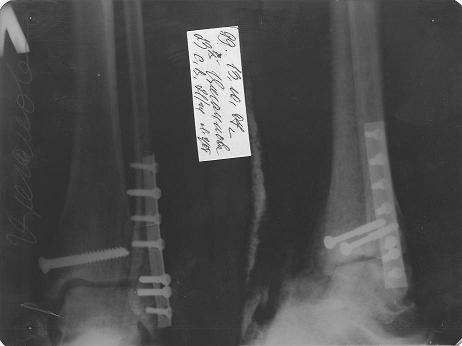

p1.JPG

Так смотрится "пирсинг" Светы, Голиков Валерий Николаевич супер!

p1.JPG (14.2 КБ) Просмотров: 7150

Идеально сопоставленные кости, даже не могу увидеть место перелома!!!